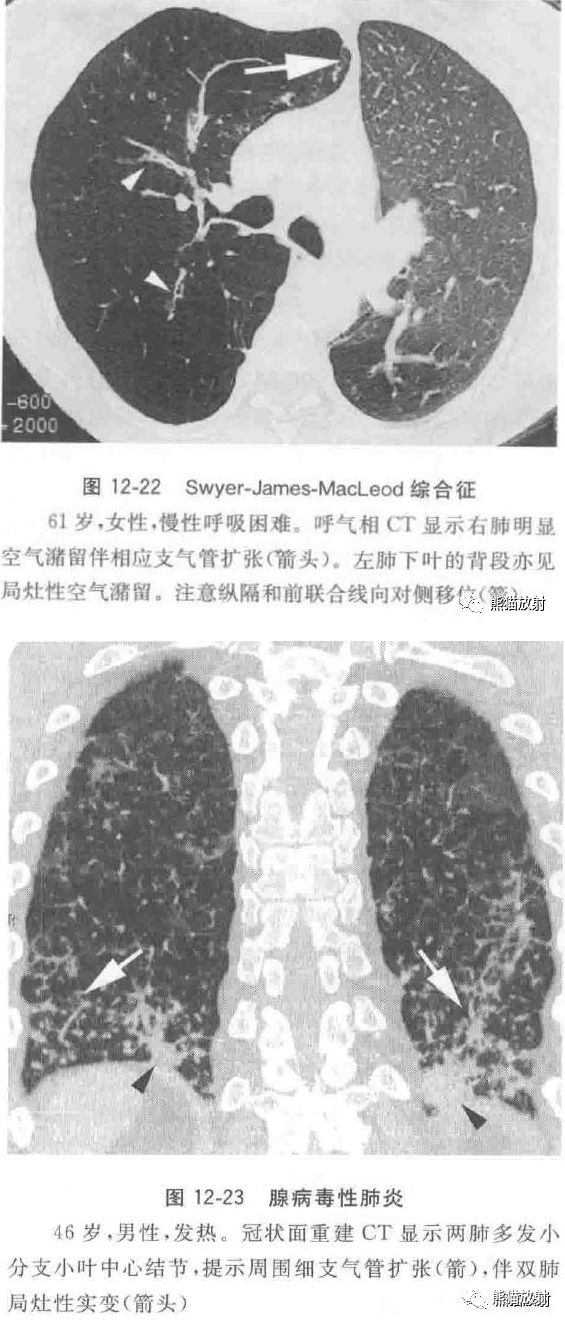

5%~10%的婴儿和儿童的急性呼吸道感染是腺病毒感染所致,成人呼吸道腺病毒感染不到1%。Swyer-James-MacLeod综合征被认为是继发于儿童腺病毒感染的感染后闭塞性细支气管炎(BO)。

感染后闭塞性细支气管炎的CT表现为肺野内边界清楚的局灶性密度增高区和密度减低区伴有肺透亮区内血管变细,细支气管管壁增厚和细支气管扩张。呼气相CT常可见到空气潴留,表现为局部边界清楚的透亮区,表明该区域肺组织的通气及灌注较差(图12-22)。

腺病毒感染越来越被认为是免疫抑制患者如干细胞或实体器官移植受者肺部感染发病率病死率的重要原因。

CT表现为两肺小叶或肺段分布的斑片状实变影,小叶中心结节和分枝状线状影和(或)两肺随机分布的磨玻璃致密影(图12-23)。